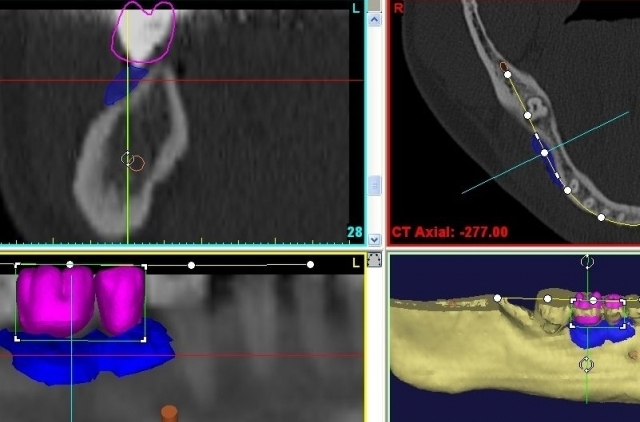

* Компютърно 3D планиране на зъбни имплантати

* Анализ на костната плътност и обем